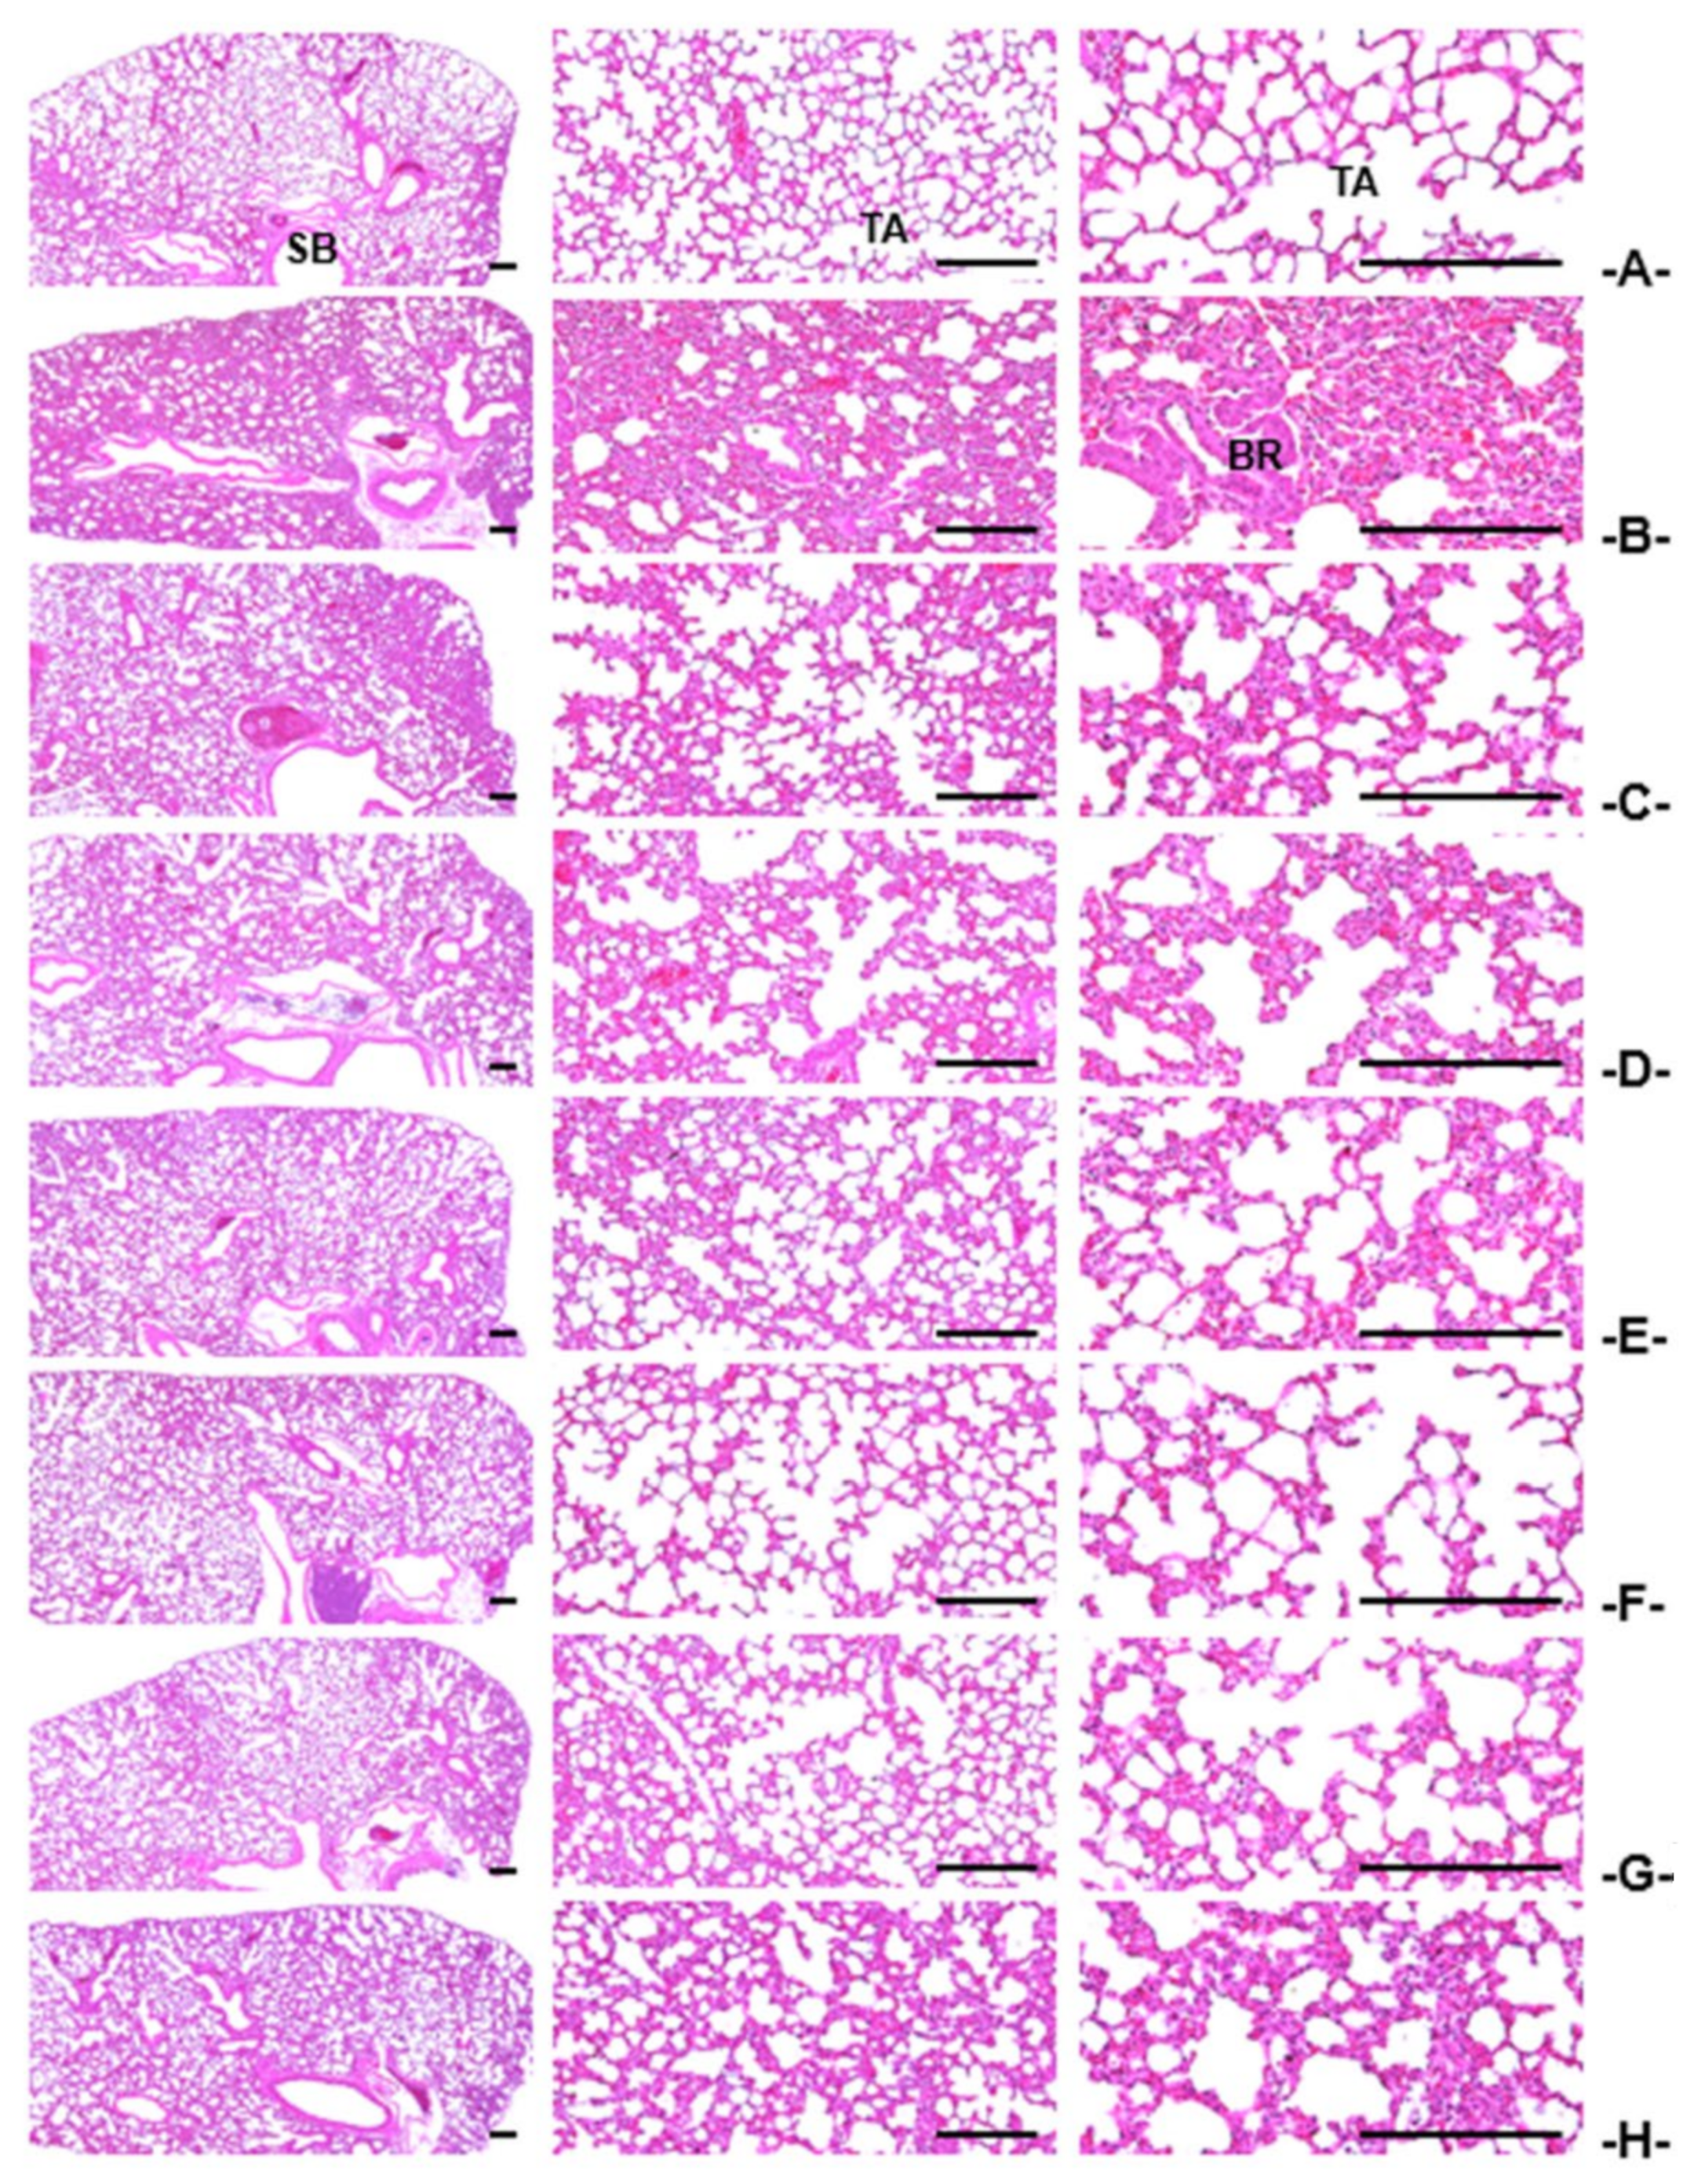

3.2.3. Histopathological Findings of the Trachea and Lung